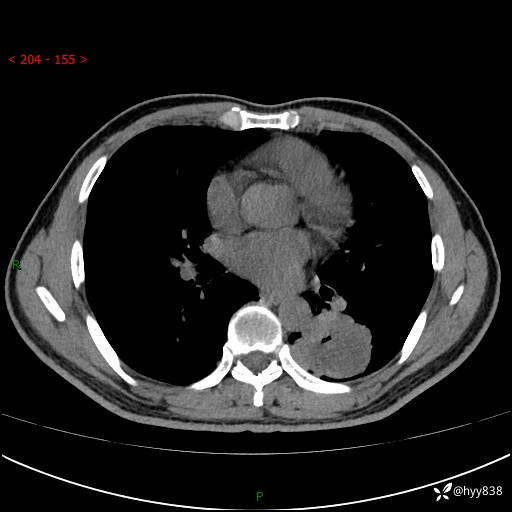

57岁/男,间断痰中带血1月余。纤支镜没有取到东西,穿刺轻松搞定---结果公布~

现病史:患者1月余前无明显诱因出现咯血症状,为痰中带血,量不大,伴轻度咳嗽,2024-3-26于当地市中医医院行胸部CT示:左肺下叶占位性病变。现患者仍有咳嗽不适,无发热乏力,无腹泻、便秘,无咳嗽,无头晕、无双下肢水肿等伴随症状,未行特殊治疗,今日患者再次出现咯血症状。患者为求进一步诊治,遂入我院,门诊以“肺脓肿”收入我科。 患者病程中,精神食欲可,二便正常,体力体重较前变化不明显。

胸部CT平扫